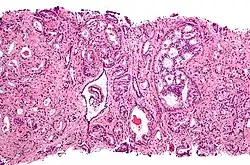

![]() Gleason grade — Lower grades are associated with small, closely packed glands. Cells spread out and lose glandular architecture as grade increases. Gleason score is calculated from grade as described in the text. |

The Gleason grading system is used to help evaluate the prognosis of patients with prostate cancer using samples from a prostate biopsy. Together with other parameters, it is incorporated into a strategy of prostate cancer staging which predicts prognosis and helps guide therapy. A Gleason score is given to prostate cancer based upon its microscopic appearance.[1]

Cancers with a higher Gleason score are more aggressive and have a worse prognosis. Pathological scores range from 2 to 10, with higher numbers indicating greater risks and higher mortality. The system is widely accepted and used for clinical decision making even as it is recognised that certain biomarkers, like ACP1 expression, might yield higher predictive value for future disease course.[2]

A pathologist microscopically examines the biopsy specimen for certain "Gleason" patterns. These Gleason patterns are associated with the following features:

- Pattern 1 – The cancerous prostate closely resembles normal prostate tissue. The glands are small, well-formed, and closely packed. This corresponds to a well differentiated carcinoma.

- Pattern 2 – The tissue still has well-formed glands, but they are larger and have more tissue between them, implying that the stroma has increased. This also corresponds to a moderately differentiated carcinoma.

- Pattern 3 – The tissue still has recognizable glands, but the cells are darker. At high magnification, some of these cells have left the glands and are beginning to invade the surrounding tissue or having an infiltrative pattern. This corresponds to a moderately differentiated carcinoma.

- Pattern 4 – The tissue has few recognizable glands. Many cells are invading the surrounding tissue in neoplastic clumps. This corresponds to a poorly differentiated carcinoma.

- Pattern 5 – The tissue does not have any or only a few recognizable glands. There are often just sheets of cells throughout the surrounding tissue. This corresponds to an anaplastic carcinoma.

In the present form of the Gleason system, prostate cancer of Gleason patterns 1 and 2 are rarely seen. Gleason pattern 3 is by far the most common.